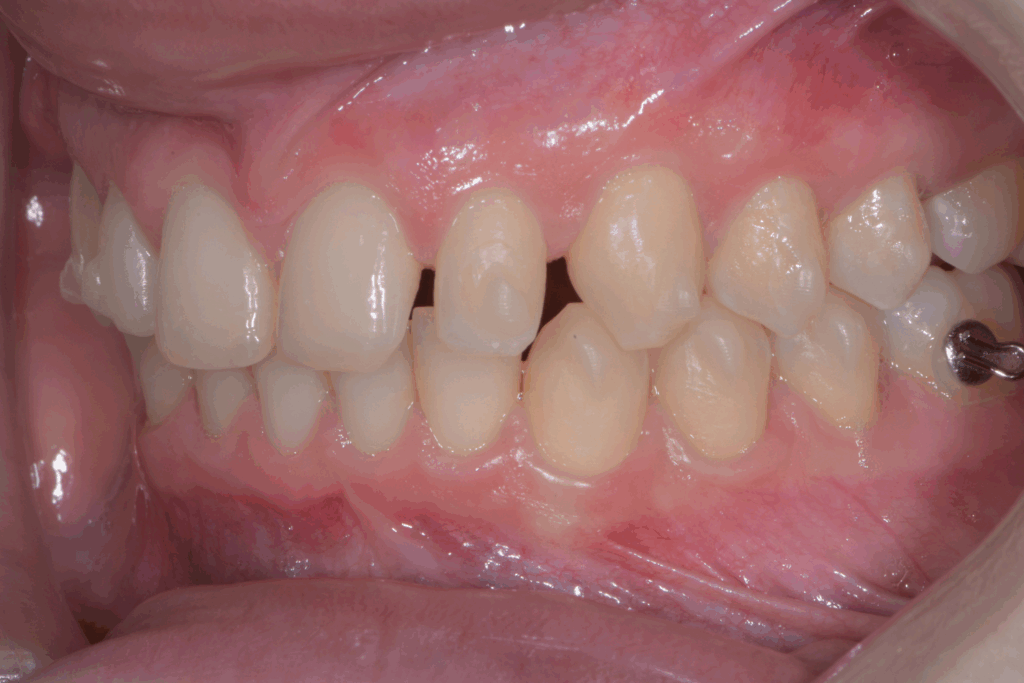

Una volta completata la fase ortodontica, siamo passati alla finalizzazione estetica degli incisivi superiori. Utilizzando la tecnica della ricostruzione in composito, abbiamo aumentato le dimensioni dei denti, migliorandone la forma e l’armonia con il resto del sorriso. Il composito, un materiale estetico e versatile, ci ha permesso di ottenere un risultato naturale e duraturo senza sacrificare la struttura dentale originale.

Risultato finale